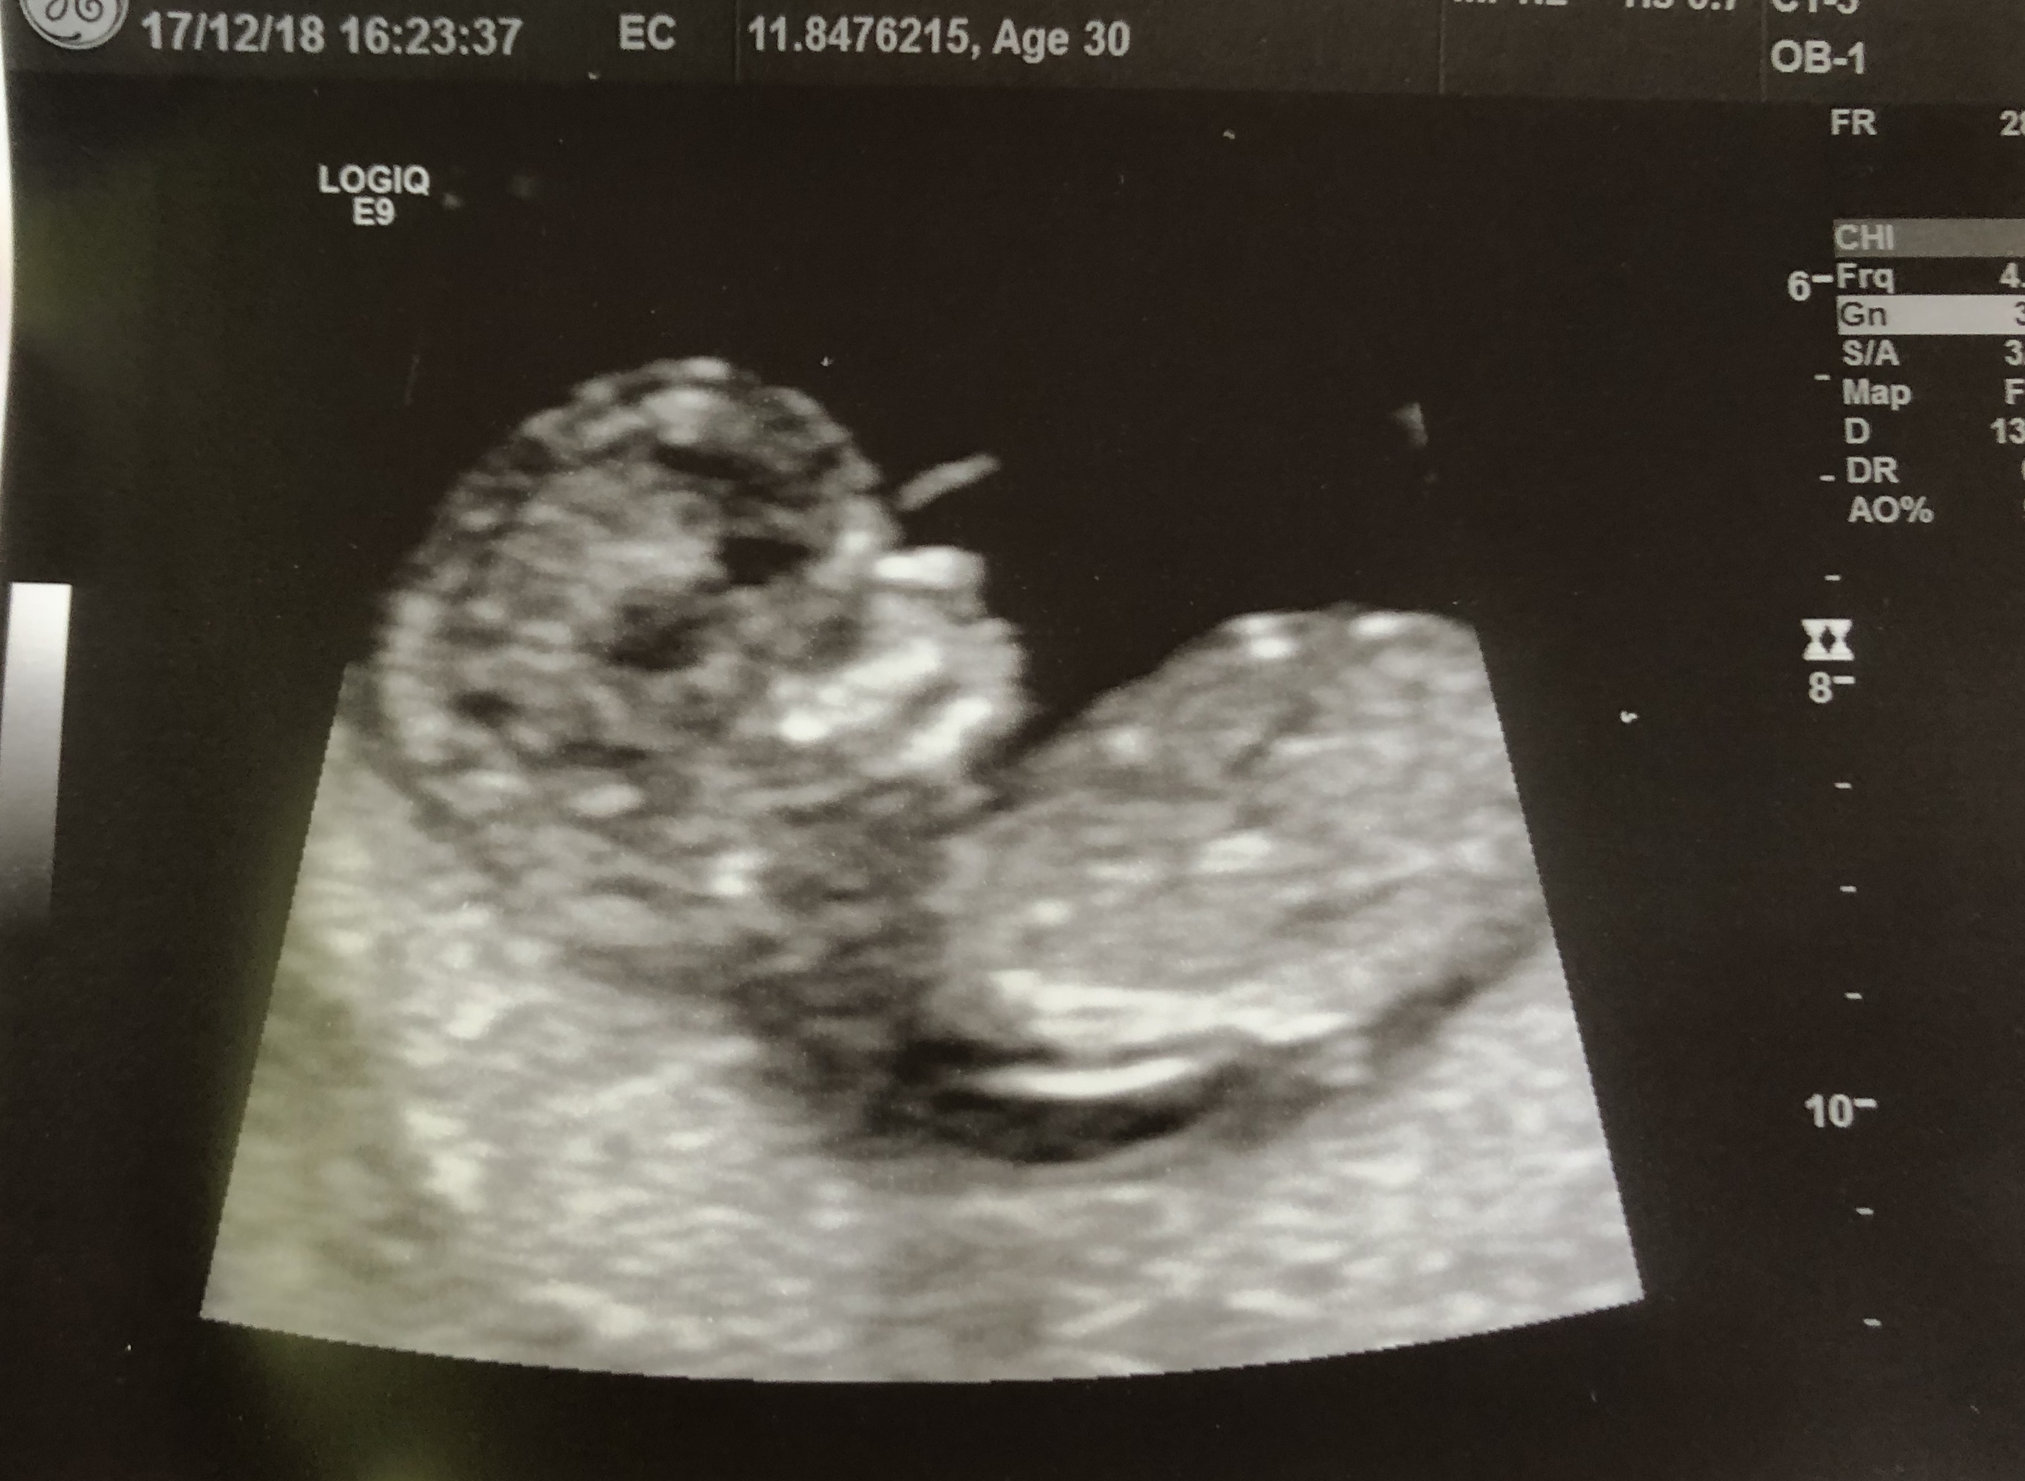

• First US on Monday, measurements have me at 10 weeks today. About a week earlier than I thought. Heartbeat was awesome to hear 😊💗. Tech did a 4D as an experiment 😁.  In love with that chubby little face already💕💕.